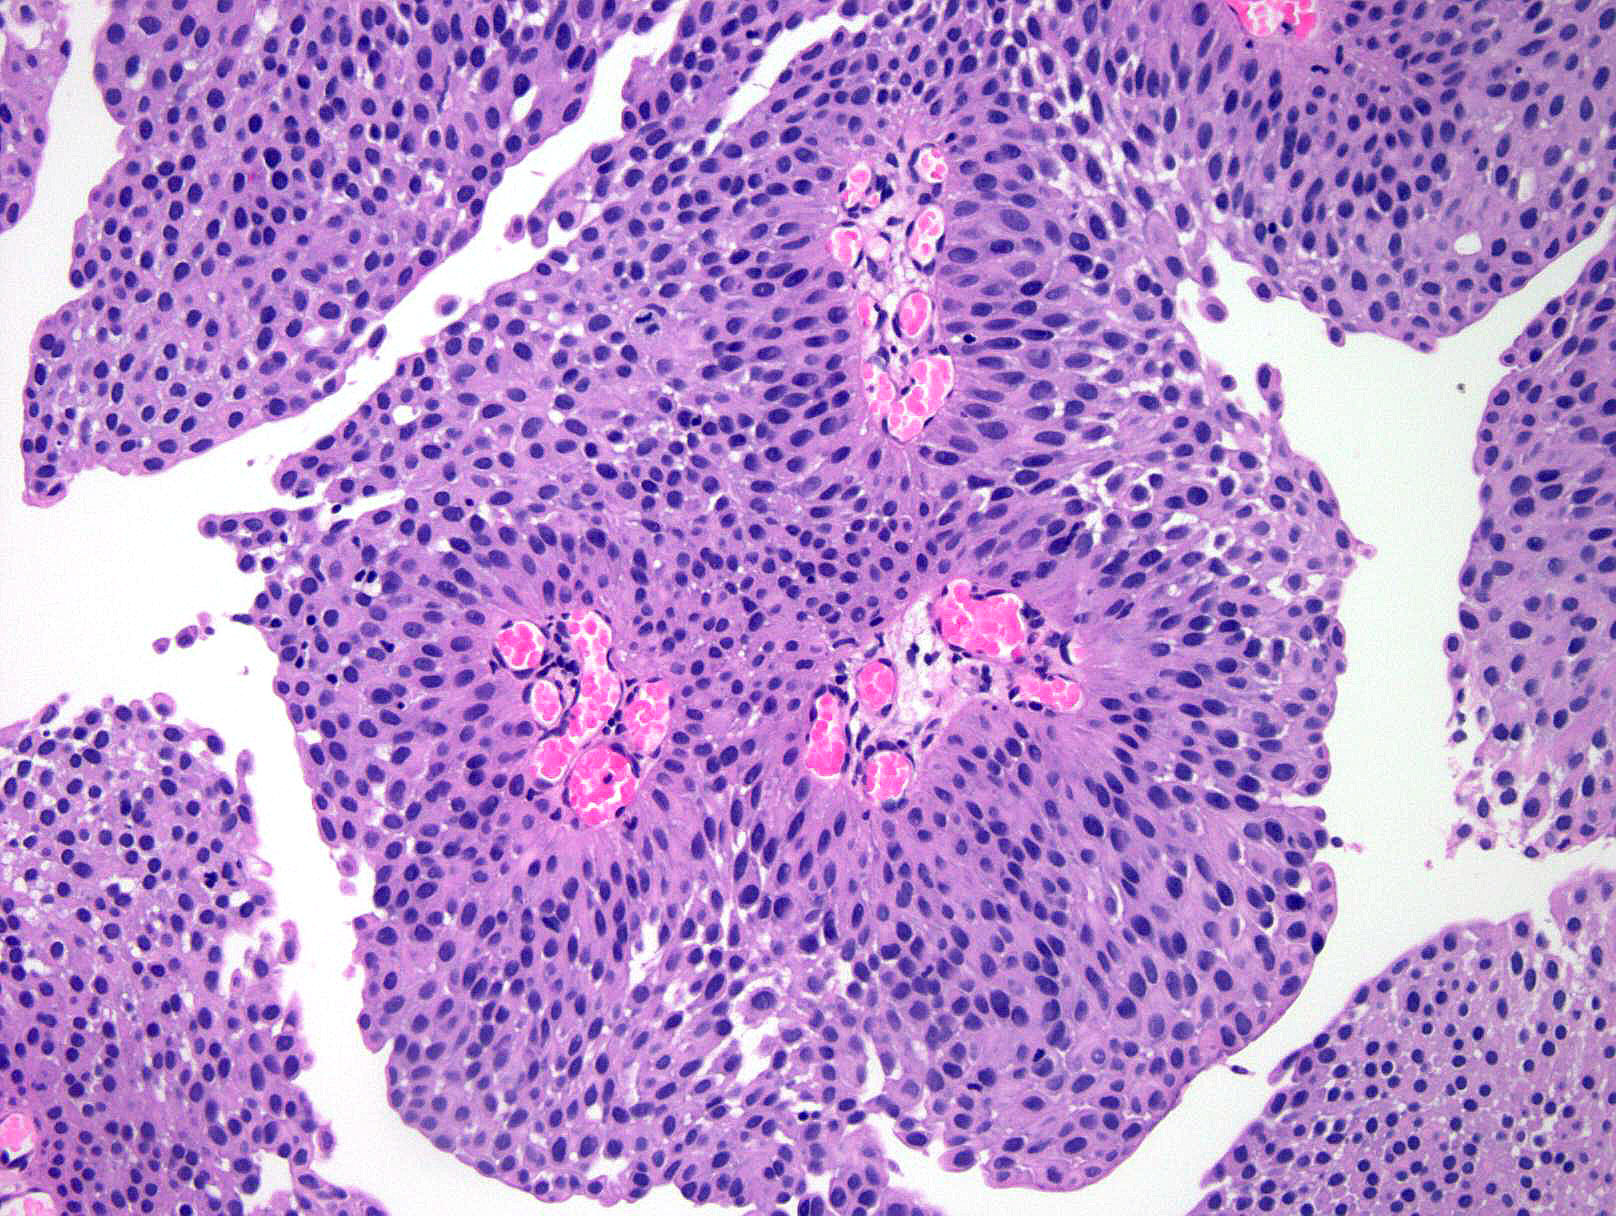

Consensus grade: Low-grade papillary urothelial carcinoma (LG-PUC)

Show diagnosis by expert panel members| User | Diagnosis | Difficulty | Comment |

|---|---|---|---|

| Pathologist 1 | Low-grade papillary urothelial carcinoma (LG-PUC) | Typical | |

| Pathologist 2 | High-grade papillary urothelial carcinoma (HG-PUC) | Typical |

Need more illustrations of this case |

| Pathologist 3 | Low-grade papillary urothelial carcinoma (LG-PUC) | Typical | |

| Pathologist 4 | High-grade papillary urothelial carcinoma (HG-PUC) | Borderline lower | |

| Pathologist 5 | High-grade papillary urothelial carcinoma (HG-PUC) | Borderline lower | |

| Pathologist 6 | Low-grade papillary urothelial carcinoma (LG-PUC) | Typical | |

| Pathologist 7 | Low-grade papillary urothelial carcinoma (LG-PUC) | Typical | |

| Pathologist 8 | Low-grade papillary urothelial carcinoma (LG-PUC) | Borderline higher | |

| Pathologist 9 | Low-grade papillary urothelial carcinoma (LG-PUC) | Typical | |

| Pathologist 10 | High-grade papillary urothelial carcinoma (HG-PUC) | Borderline lower | |

| Pathologist 11 | High-grade papillary urothelial carcinoma (HG-PUC) | Typical |

difficult to say on one slide, but would go for a high grade, quite a lot of atypia |

| Pathologist 12 | Low-grade papillary urothelial carcinoma (LG-PUC) | Borderline higher | |

| Pathologist 13 | Low-grade papillary urothelial carcinoma (LG-PUC) | Typical | |

| Pathologist 14 | High-grade papillary urothelial carcinoma (HG-PUC) | Borderline lower | |

| Pathologist 15 | Low-grade papillary urothelial carcinoma (LG-PUC) | Borderline higher | |

| Pathologist 16 | Low-grade papillary urothelial carcinoma (LG-PUC) | Typical | |

| Pathologist 17 | Low-grade papillary urothelial carcinoma (LG-PUC) | Bordering on lower |

the urothelium is thickened,distribution of nuclei is more uneven, have variable nuclear enlargement and hyperchromasia ,mitosis can be seen. |

| Pathologist 18 | Low-grade papillary urothelial carcinoma (LG-PUC) | Typical |

No specific comment. |

| Pathologist 19 | Low-grade papillary urothelial carcinoma (LG-PUC) | Typical | |

| Pathologist 20 | Low-grade papillary urothelial carcinoma (LG-PUC) | Typical | |

| Pathologist 21 | High-grade papillary urothelial carcinoma (HG-PUC) | Bordering on lower | |

| Pathologist 22 | Low-grade papillary urothelial carcinoma (LG-PUC) | Bordering on higher | |

| Pathologist 23 | Low-grade papillary urothelial carcinoma (LG-PUC) | Typical |

Case description (by case creator):

DH PAP6